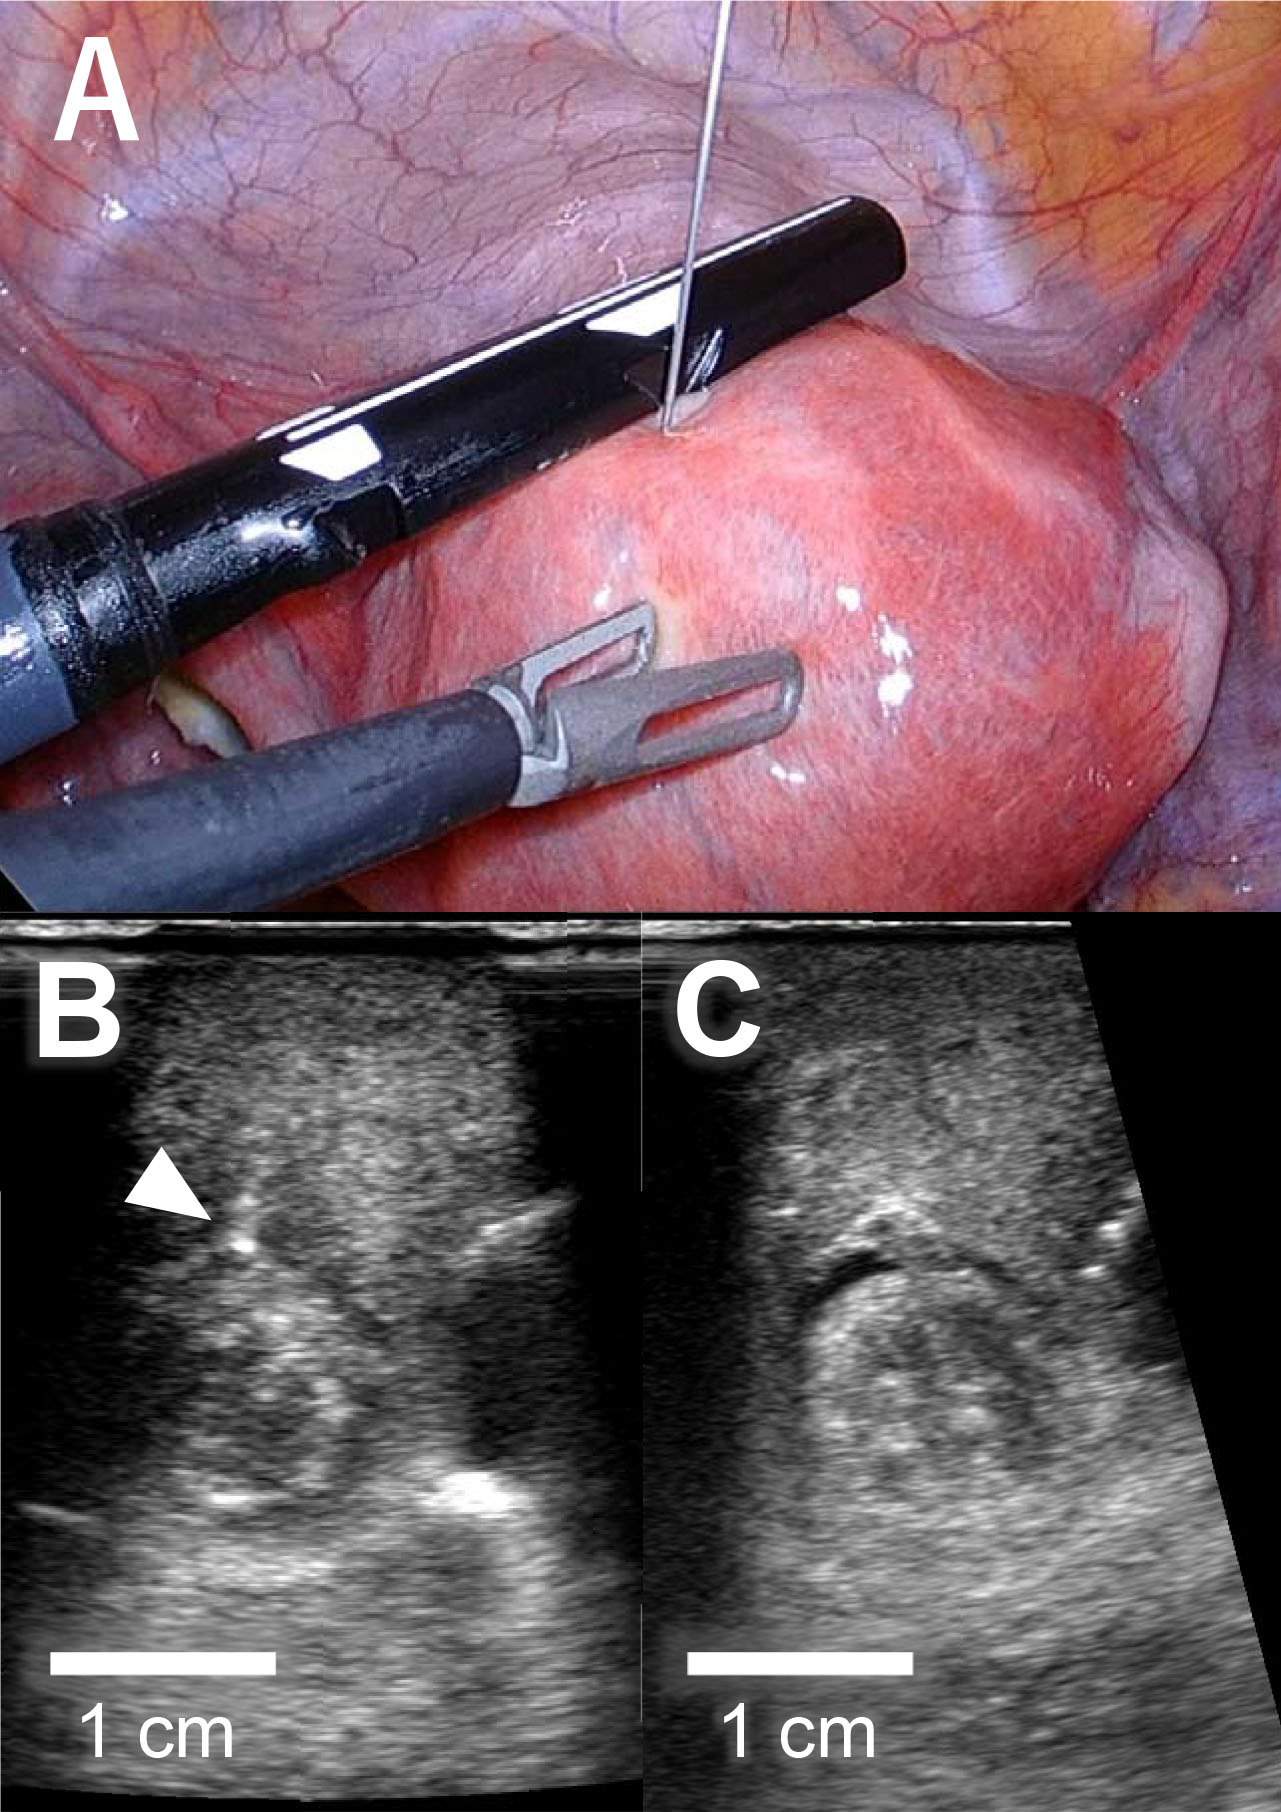

A 36-year-old nulligravida woman visited our clinic for an evaluation of her infertility. She was healthy, and her menses were regular and normal. Transvaginal ultrasonography revealed a type 2 submucosal myoma with a 60% myometrial extension measuring 15 mm in the anterior uterine wall and a type 4 intramural myoma (classified via guidelines from the International Federation of Gynecology and Obstetrics) measuring 49 mm in the posterior uterine wall. Magnetic resonance imaging suggested that the posterior myoma was a cellular leiomyoma (Fig. 1A). To make a definitive diagnosis regarding the intramural myoma, we planned a laparoscopic myomectomy. Furthermore, we planned to laparoscopically resect the submucosal myoma considering the myoma’s negative effect on implantation. Since the submucosal myoma was not visible from the external side of the uterus, we planned to use LUS to detect it. The location of the submucosal myoma was preoperatively assessed by transvaginal ultrasound sonography and magnetic resonance imaging. We measured the depth from the external side and the distance from the midline and fundus of the uterus. During the surgery, we used an ultrasound machine (Aplio a verifia CUS-AA000, Canon Medical Systems, Otawara, Tochigi, Japan) and a transducer (Linear array transducer PET-805LA, Canon Medical Systems, Otawara, Tochigi, Japan) with the detection frequency set at 7.0 MHz. We inserted the transducer through a 12-mm trocar (Fig. 1B). The submucosal myoma was visualized successfully with LUS immediately after the transducer was placed on the anticipated area of the anterior wall. Vasopressin (2 units diluted in 10 mL of saline) was injected precisely between the myoma and the myometrium under ultrasonography guidance (Fig. 2A,B). LUS also confirmed that the injected vasopressin effectively spread between the myoma and the myometrium (Fig. 2C). Using laparoscopic forceps and monopolar cautery, both the submucosal and the intramural myomas were successfully removed from the uterus without breaching the endometrium (Fig. 3A,B). The myomas were morcellated in a bag so that small fragments would not be scattered into the peritoneal cavity. The myoma beds were sutured to double to triple-layer closure with absorbable surgical thread. The postoperative course was uneventful, and the patient was discharged from the hospital as scheduled. No abnormal signs were detected at hospital visits 1 and 3 months after the surgery, and the initiation of fertility treatment was planned for 6 months after the surgery.

Fig. 2.Injection of vasopressin during laparoscopic myomectomy. (A) Intraperitoneal image during laparoscopic surgery. Diluted vasopressin was injected under ultrasonography guidance. (B) Injection needle (white arrowhead) was inserted to the boundary between the myoma and the myometrium. (C) Injected vasopressin spread in the layer between the myoma and the myometrium.